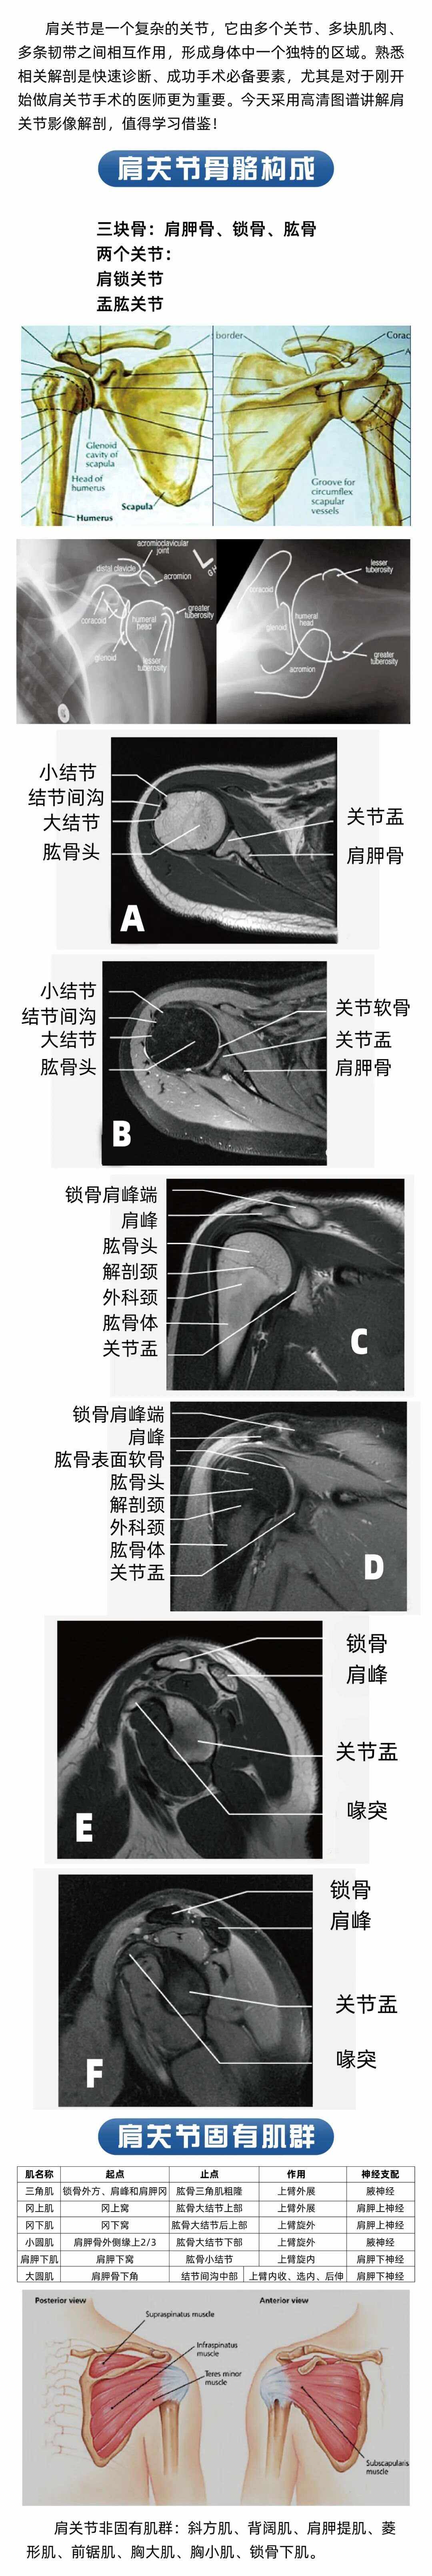

肩关节的功能解剖学习笔记肩关节概述 肩关节是一个浅的球窝关节,其结构特点使得它具有较高的灵活性,但同时也相对不稳定肱骨头相当于高尔夫球与肩胛盂相当于球座之间的关系,更形象地比喻为海狮用鼻子顶着一个球保持平衡,这一描述生动地展现了肩关节在保持功能性和稳定性方面的挑战静。